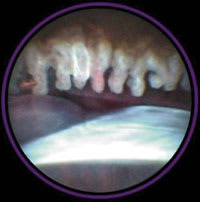

Image taken with three port probe and lens with 70� field of view that enables direct visualization of th ciliary body. |